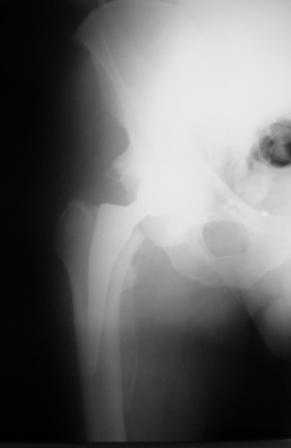

Больной Т. 56 лет, Диагноз: двухсторонний коксартроз 3-4 ст справа, 1-2 ст слева 2.10.08 выполнена операция тотальное бесцементное эндопротезирование. Использовался наружный доступ, положение на боку. Операция протекала без особенностей.

Выполнен послеоперационный ренгеноконтроль в прямой проекции. Рана зажила.

Больное выписан. Рекомендована ходьба без нагрузки 6 нед, рентгеноконтроль через 2 мес. Явка на консультацию На консультации через 7 недель- Больной ходит с дозированной нагрузкой, умеренные боли по задней поверхности правого бедра. Планируется ревизия. Удаление ножки. Установка такой же ножки Corail.

Приходилось ли кому встречаться с такой ситуацией? Вопросы: вросла ли ножка? Какие могут возникнуть сложности с удалением ножки? Нужна ли будет дополнительная трепанация диафиза? И как? Правильный выбор ножка Corail для ревизии в такой ситуации?